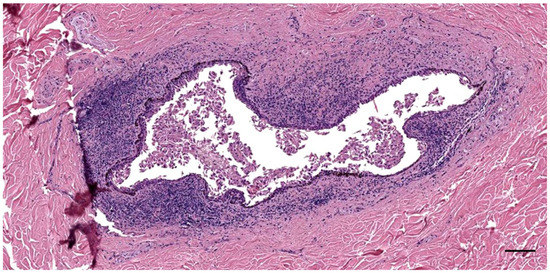

3.2. Nodular Lymphoid Tissue

4.2. Ear Canal Lymph Node